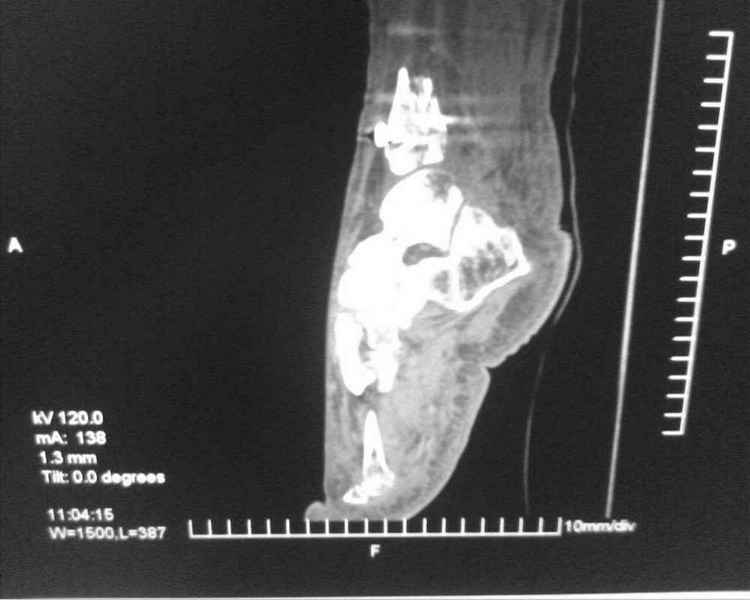

[Ortho] [1/2] Метатарзал краш синдром в порочном сращении (эквинусная стопа), несращение сегментарного перелома костей голени после БИОС , ПТФБ, ХВН СЕАР С-6.

Больной 39 лет. Травма получена в ДТП 21.09.09г. был госпитализирован в обл. больницу

соседней области с диагнозом сочетанная травма зчмт сотрясение головного мозга

сегментарный перелом костей правой голени с\3-н\3, суральный флеботромбоз циркулярные

некрозы н\3 правой голени правого голеностопного сустава лечение скелетным вытяжением за

пяточную кость. переведён в наше отделение 6.10.09г. возобновлено скелетное вытяжение,

перевязки, иссечение некрозов, антикоагулянты. На уздг диагноз флеботромбоза

подтвержден. 28.10.09 операция БИОС правой б\берцовой кости штифтом PTNL остеомед .

остеосинтез м\берцовой кости не выполняли из-за наличия гранулирующих ран и некрозов в

месте операционного доступа. Вторым этапом планировалось наложить аппарат Илизарова для

выведения стопы из эквинуса и динамизации штифта. Но из-за наличия гранулирующих ран и

некрозов в местах проведения спиц на стопе и голени 19.11.09 переведен в ожоговое отделение

для САДП гранулирующих ран после некрозов. 23.11.09 САДП. В послеоперационном периоде-

длительное заживление ран с лизисом кожных лоскутов, манифестное развитие ХВН с

формированием трофических язв и лимфэдемы. Больной явился на госпитализацию 13.01.10г.

локальный статус и свежие снимки прилагаю. Данные уздг выложу позже. Что в этой ситуации

делать я не знаю. Признаков сращения на Rg-нет плюс метафизарный фрагмент кивнул на вальгус.